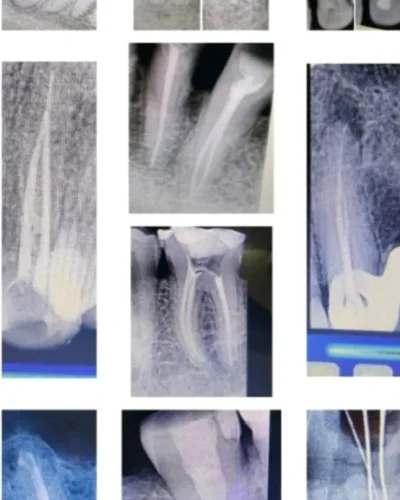

Endodontic Treatments (Root Canal & Re-Root Canal Therapy)

Root Canal Therapy

Toothache can be excruciating – but tooth extraction isn’t your only option. Root canal therapy removes infection and preserves your natural tooth, and with Dr. Shreya, a trusted Endodontist in Noida, patients receive advanced and compassionate care.